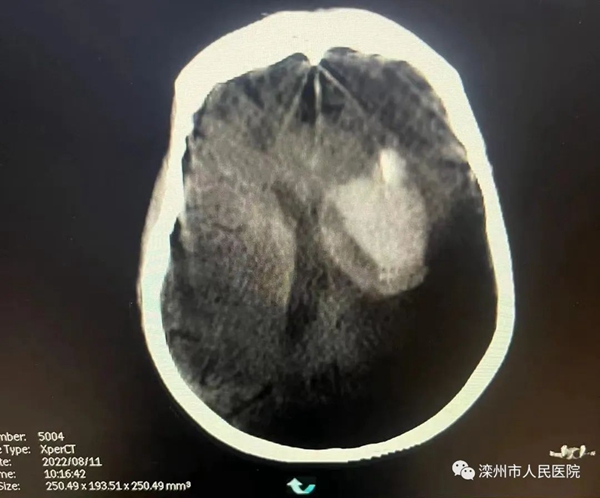

术中CT影像

经过医生熟练的操作后置入引流管,回吸见暗红血性及凝血块液吸出。C型臂检查示引流管位置良好,缝合固定引流管,引流管接脑室外引流器,手术顺利,术后患者状态良好。